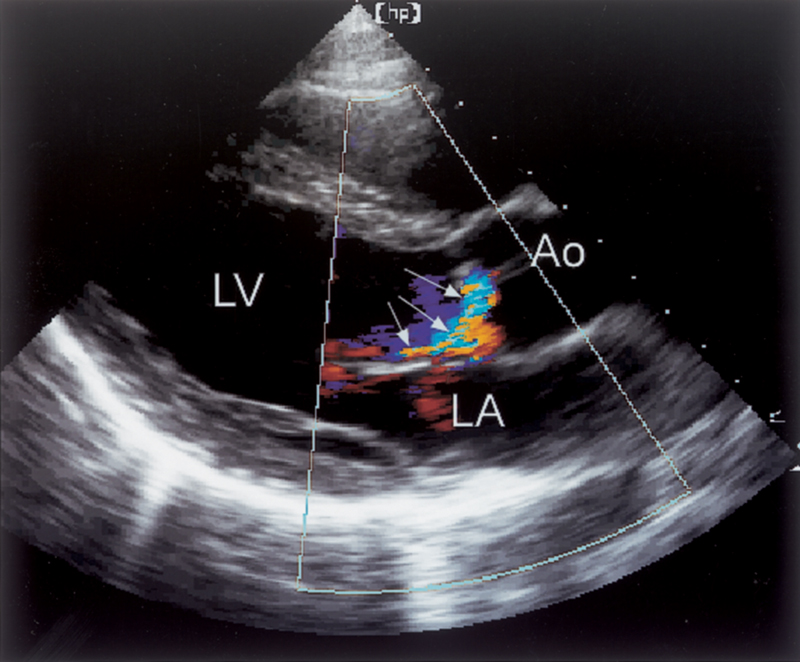

فحوصات تشخيصية لبعض امراض القلب والشرايين التاجية